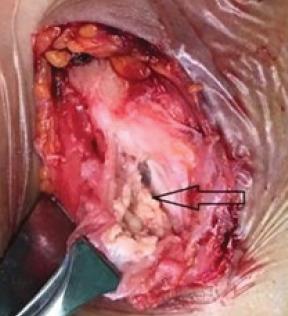

A 39-year-old female (right hand dominant) presented with the left elbow pain for the past 1 year. The diagnosis was achieved by radiography and confirmed by histopathology. Her pain did not respond to conservative treatment of analgesics, physiotherapy, and elbow support and a local steroid injection. She, therefore, underwent surgical exploration of the elbow, under general anesthesia. There was white-colored paste like a collection within the common extensor tendon origin, with dystrophic calcification of the tendon. The histology of the excised tissue revealed focal nodular aggregates of plump fibroblasts and osteoclastic giant cells around microcalcific foci. Large areas of fibrosis and calcific nodular deposits seen suggestive of calcific tendonitis.

一名39岁女性(右手为优势手),过去1年出现左肘疼痛。通过X线摄影确诊,并经组织病理学证实。她的疼痛对镇痛药、物理治疗、肘部支撑以及局部类固醇注射等保守治疗均无反应。因此,她在全身麻醉下接受了肘部手术探查。在伸肌总腱起点处有白色膏状物质聚集,肌腱存在营养不良性钙化。切除组织的组织学检查显示,微钙化灶周围有丰满的成纤维细胞和破骨巨细胞形成的局灶性结节状聚集。可见大片纤维化和钙化结节沉积,提示钙化性肌腱炎。